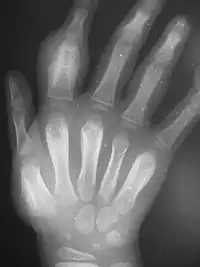

| Nodules on the elbow resulting from a Treponema pallidum pertenue bacterial infection | |